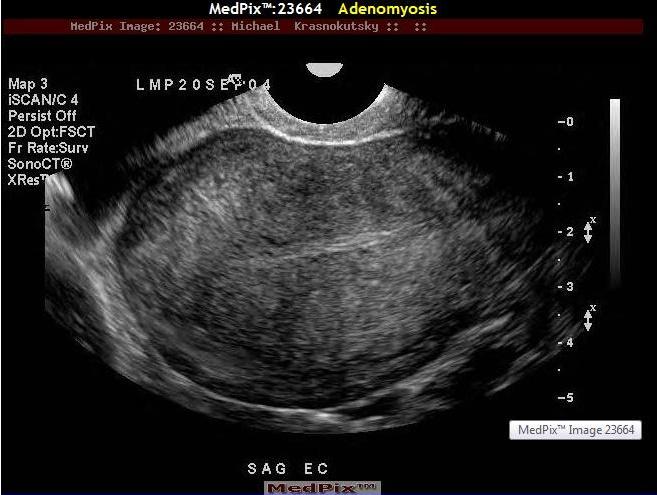

Adenomyosis

Glándulas de tejido endometrial que crecen en el miometrio

Visto en mujeres luego de los 40 años

Síntomas: dismenorrea y

sangrado anormal

Se ha asociado con alza en estrógeno

Por sonografía: Útero Grande e hipoecoico

especialmente durante

la menstruación.

Se diagnostica con facilidad con MRI